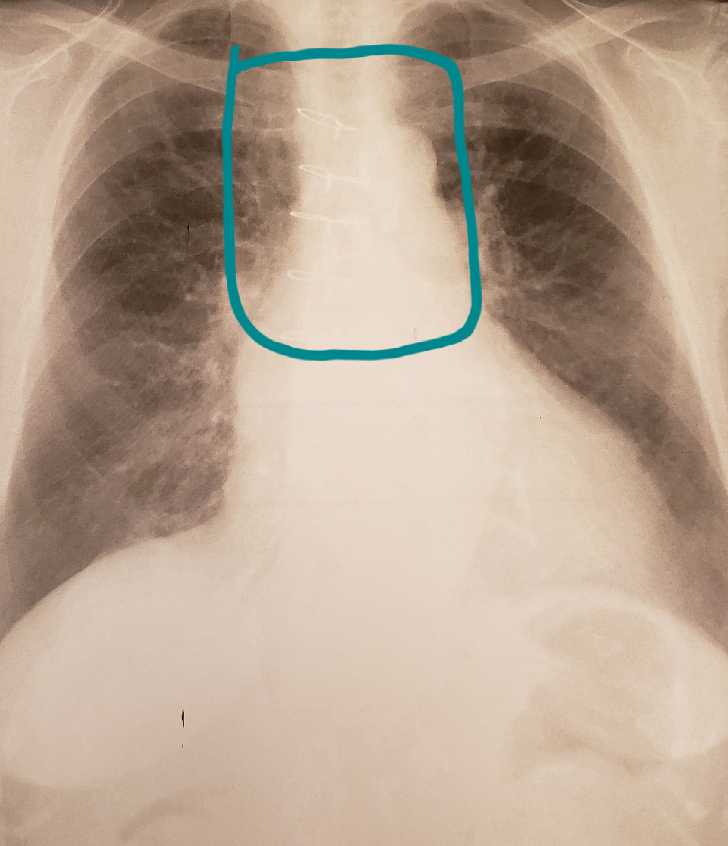

1つは、 レントゲンに白い影が映ったからといって、肺がんであるとは限らない ということ。 私のように、痰が原因の場合だってある。 ドラマなどでは、医者が「白い影」といったらそれはもう肺がんと相場が決まっているが、現実は必ずしもそうではMar 17, 16 脊髄に白い影?脊髄空単純レントゲン写真 質問:腰のレントゲンで正常といわれましたが,腰痛が強く薬を飲んでも治ら ないので,一度だけ行ってやめてしまいました。どうすればよいのでしょう。 一生腰痛が続くのでしょうか? 回答:これは,よく起こる誤解です。 病気 腰痛があり、腰のレントゲンを撮ったのですが、その時縦に長いくっきりした白い影が写りました。 私がみてわかるような腰椎2~3個くらいの長さがありました。 造影剤の既往を聞かれましたが、2年前

医者から 肺に白い影が見える と言われてct検査を受けた結果 ロケットニュース24

レントゲンで肺炎などはありませんか 母 84 が本日撮 Yahoo 知恵袋